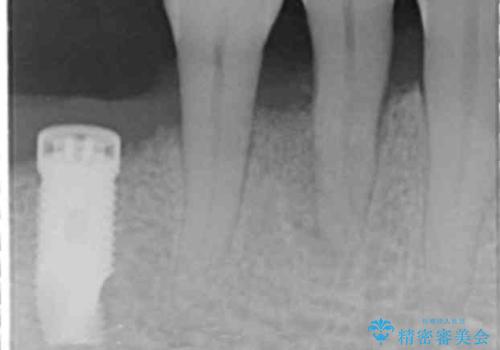

精査したところ、全顎的な重度の歯周病により右下の小臼歯(右下4)激しい動揺を認めました。

できるだけ自分の歯を残したいという患者様の強いご希望により、禁煙指導後再生療法(骨を増やす手術))を行いました。

再生療法から1年後リエントリー手術により骨の再生を確認し、骨外科処置(骨を平らにして歯周ポケットの根本的な改善を図る処置)を行ったのち、連結補綴を行いました。

再生療法と骨外科処置により、歯周ポケットは全周2mm以下に改善されました。